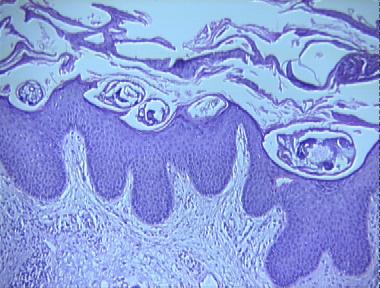

norwegian scabies

Histologic Features